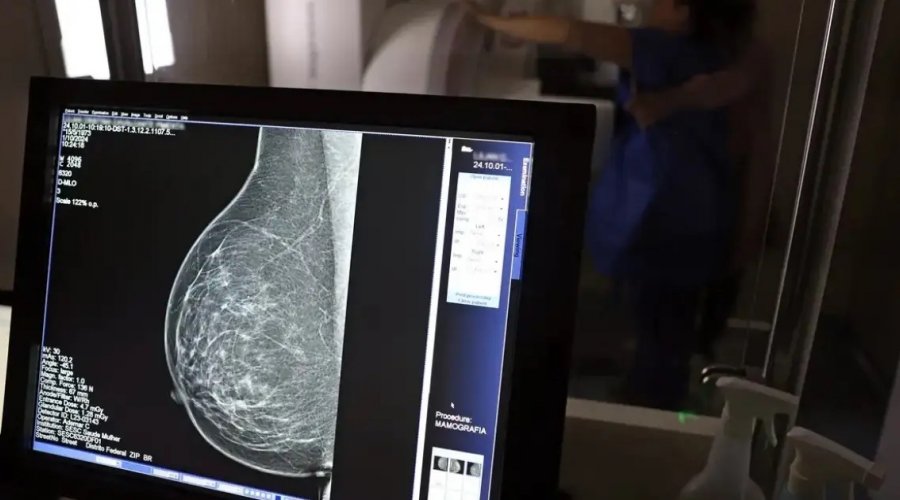

Foto: José Cruz/Agência Brasil

Uma mudança significativa na legislação de saúde foi sancionada, ampliando o direito à reabilitação de pessoas que passam por mastectomia em razão do câncer de mama. A nova norma atualiza a Lei nº 9.797/1999, que antes assegurava apenas a cirurgia plástica reconstrutiva, e agora torna obrigatório o acesso ao tratamento fisioterapêutico.